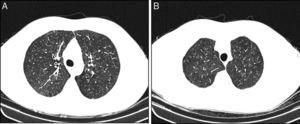

The medical records of patients diagnosed with RB-ILD during the period of January 2008 to July 2013, followed in ILD outpatient clinic at Centro Hospitalar S. João, were retrospectively reviewed. RB-ILD diagnosis was based on 2002 American Thoracic Society/European Respiratory Society International Multidisciplinary Consensus Classification of the Idiopathic Interstitial Pneumonias.6 Fifteen patients were included with a mean age of 48 (29–65) years and 13 (86.6%) were male. All of them were heavy cigarette smokers (median: 46.3 pack-year). Most patients (73.4%) have mild symptoms, dyspnea on exertion (n = 8/53.3%) and cough (n = 7/46.6%) were the only symptoms identified. Typical centrilobular ground-glass nodules predominantly in the upper lobes were the overall pattern on the HRCT (Figure 1). Concomitant upper lobe centrilobular emphysema was identified in 5 (33.3%) patients. Pulmonary function tests showed a slight obstructive impairment (median FEV1 – 76%) associated with a normal median value in the diffusion capacity (median DLCO – 76%), although there was a minor decrease (DLCO – 61–75%) in six patients. BAL was performed in 12 patients and besides the increased cellularity associated with the intense brown pigment-laden macrophages (Figure 2), two (16.6%) had mild neutrophilia and another two mild eosinophilia. Three patients were submitted to surgical lung biopsy, two of them performed during the context of cardiothoracic surgeries not related with RB-ILD and the other one during a video-assisted thoracoscopic surgery for pneumothorax with a persistent air-leak. All patients were referred to smoking cessation programs but only three gave up, the remainder just reduced the amount of tobacco consumption. None of them had any additional therapeutic interventions besides inhaled bronchodilators prescribed to those patients that were more symptomatic. Regardless of whether they maintained smoking habits, after a mean follow-up of 49 (12–72) months, all the patients included remained clinically stable, with similar functional (mean FEV1 – 74% and DLCO – 75%) and radiological features.

Figure 1. Axial CT images show ill-defined centrilobular ground glass nodules with predominant upper lobe distribution. Areas of paraseptal emphysema are present.